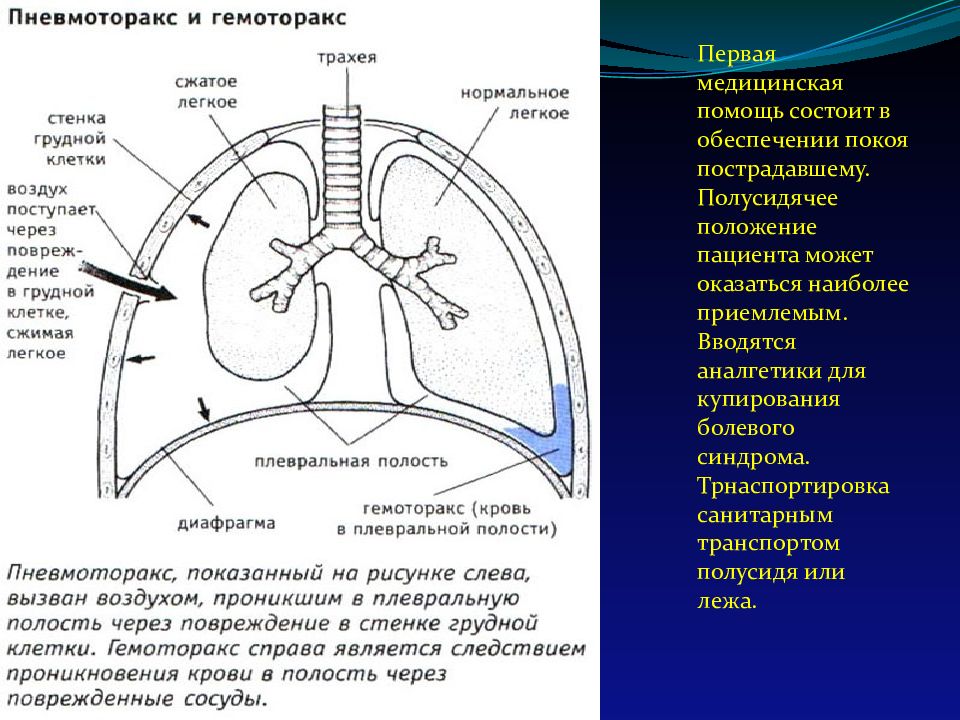

Схемы дыхания: Пневмоторакс на изображениях